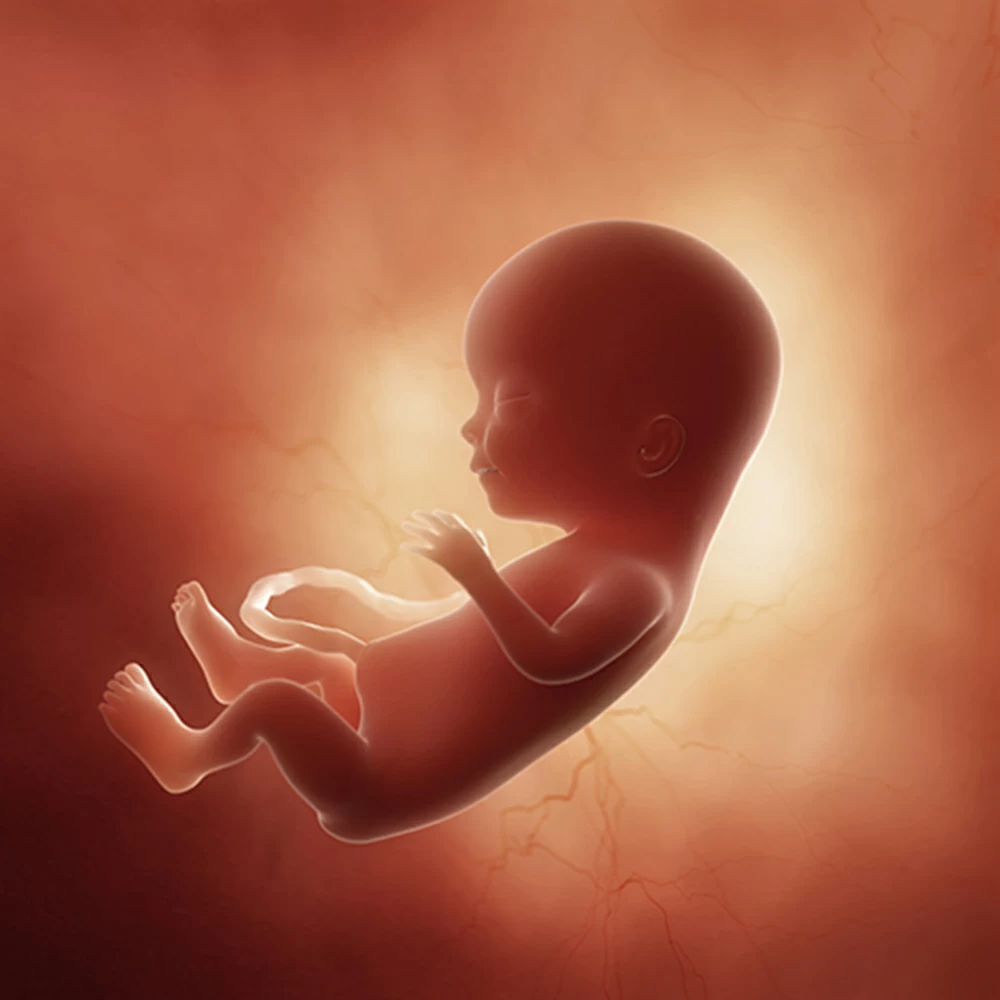

Тело плода остается непропорциональным: мелкое туловище, большие размеры головы, длинные руки и короткие ноги, согнутые во всех суставах и прижатые к животу.

Копчиково-теменной размер плода составляет около 10 см, вес плода – 70-75 грамм. Голова по-прежнему остается достаточно большой, но рост рук, ног и туловища начинает ее опережать.

На 22 неделе размеры плода увеличиваются до 28 см, вес – до 450-500 грамм. Размеры головки становятся пропорциональны туловищу и конечностям. Ноги практически все время находятся в согнутом состоянии.